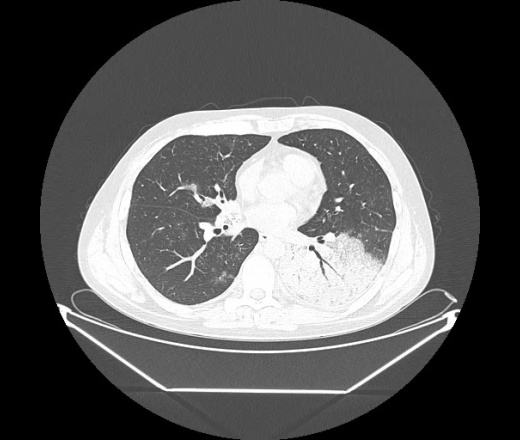

М. 1984 г.р.  Лихорадка 39, кашель , одышка.. и надоевший всем вопрос- "типично ли для ковид?" ( в настоящее время на него обязательно нужно дать ответ в своем протоколе)

На мой взгляд нетипично для ковид: много центрально-расположенных поражений, лобарное поражение нижней доли слева. 50/50

Не типичая картина для ковид.

КТ-признаки двусторонней бактериальной пневмонии.

Все верно, здесь абсолютно нетипичная картина, несмотря на матовое стекло с ретикулярными изменениями, но почему-то  посчитали иначе. Кстати,  "малыша" не заметили)?

Добавил 6 день

Что за малыш? Будущий абсцесс? Не заметил. Только о туберкулёзе подумал

+ 1?  Зона очень похожа была на формирующийся абсцесс, даже по рентгенпризнакам. Еще хотела спросить, но постеснялась. А на контроле видно

да, это я о абсцессе.